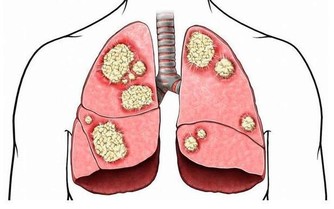

癌症一般是指惡性腫瘤,腫瘤是指機體在各種致瘤因子的作用下,局部細胞組織增生所形成的新組織。它有一個特點,它的生長不受正常機體的生理調節,而是破壞正常的組織和器官。我們所謂的癌症,也就是惡性腫瘤和良性腫瘤相比,具有以下幾個特徵。第一個是生長速度,第二個是容易發生轉移,特別是發生轉移以後,腫瘤的危險性就大大地增加。第三,容易復發。第四,復發最終會導致患者多髒器受損,最終導致患者死亡。

腎臟也一樣,在長期工作壓力和毒素的接觸下,腎臟,尤其是尿液流經的腎小管上皮細胞會發生一些量變,從量變轉變到質變。這時候就產生了腎臟最初的病變。在發生最初病變的時候,隨著病變不斷地長大,這種生長逐漸失去調控,就形成了腫塊,也就是說腎臟上長了一些我們所說的惡性腫瘤。

腎臟的惡性腫瘤分為很多種,最常見的就是腎細胞癌。